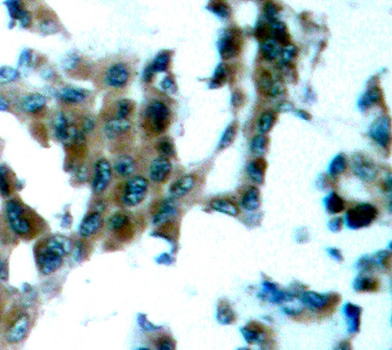

• AP0192: image 2

Immunohistochemical analysis of paraffin-embedded human lung carcinoma tissue using Phospho-PRKCQ-S695 antibody.